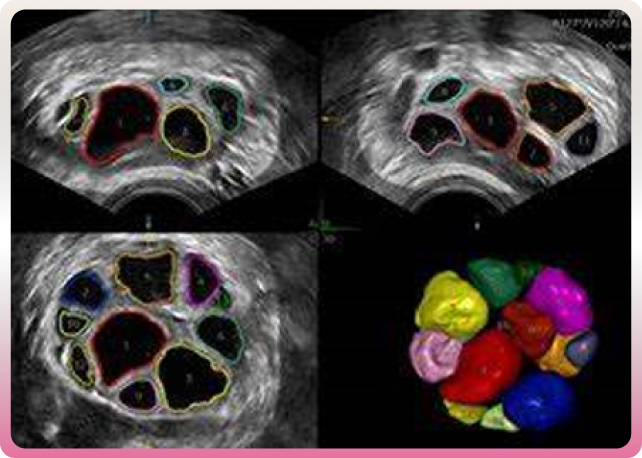

Dans un premier temps, on pratique une stimulation ovarienne. Les traitements de stimulation ovarienne permettent de stimuler l’ovulation afin d’obtenir une maturation suffisante de plusieurs follicules dans les ovaires puis de prélever plusieurs ovocytes mûrs afin de permettre leur fécondation. Des dosages sanguins hormonaux sont effectués chaque jour, dans un même laboratoire de référence, afin d’évaluer la qualité de la sécrétion hormonale des follicules. Une échographie permet de surveiller la réponse au traitement et de contrôler la croissance folliculaire.

-Maturation des follicules

La deuxième étape est le déclenchement de la stimulation. Il s’effectue lorsque le nombre et la taille des follicules sont satisfaisants et les dosages hormonaux suffisants. Une injection d’hormone HCG est alors effectuée 34 à 36 heures avant la ponction d’ovocytes. Le médecin repère les follicules mûrs lors de l’échographie et en aspire leur contenu, à l’aide d’une aiguille placée dans le vagin en direction des ovaires.